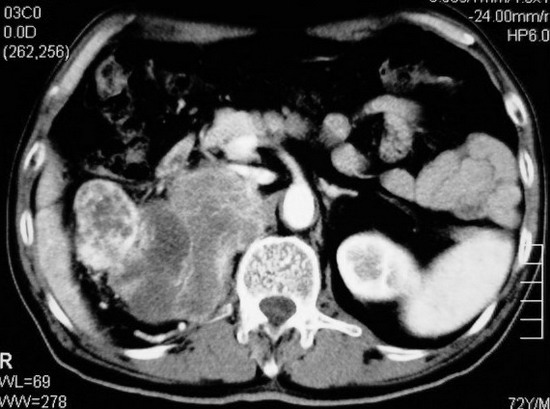

以下是引用杀毒软件在2008-11-17 19:15:00的发言:[br]考虑------右肾癌合并肾静脉---同侧肾上腺受侵可能性大

以下是引用zjzjr在2008-11-17 20:45:00的发言:[br]考虑------右肾癌合并肾静脉---同侧肾上腺受侵可能性大及腹膜后淋巴结转移.